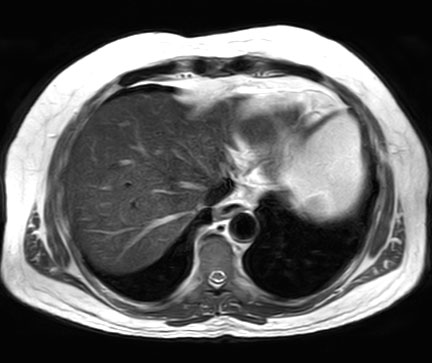

T2w TSE